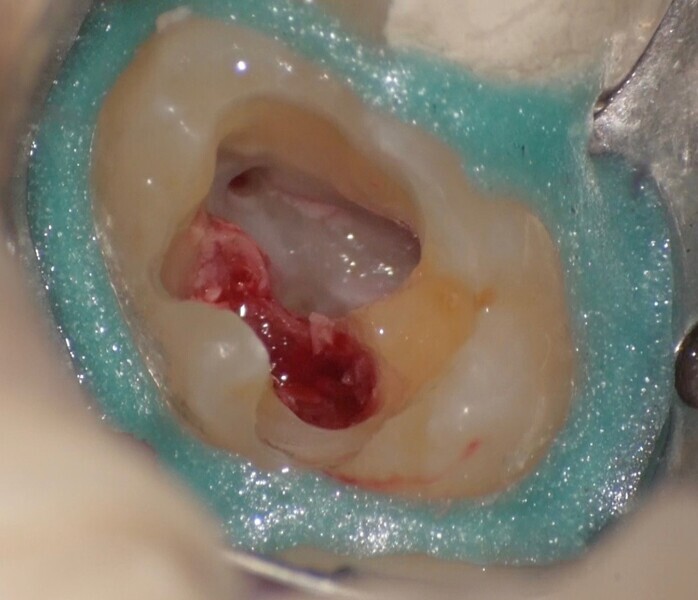

Use of 3D technology in the diagnosis and treatment of endodontic disease